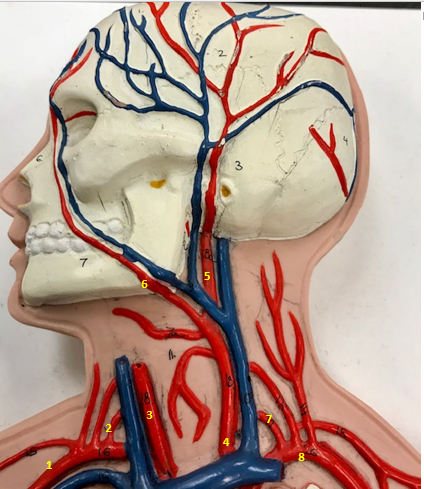

Right subclavian artery

Name #1

Supplies blood to right arm and shoulder

Function of right subclavian artery (1)

Right vertebral artery

Name #2

Supplies blood to brain and spinal cord

Function of right vertebral artery (2)

Right common carotid artery

Name #3

Supplies blood to right neck and head

Function of right common carotid artery (3)

Left common carotid artery

Name #4

Supplies blood to left neck and head

Function of left common carotid artery (4)

Left external carotid artery

Name #5

Supplies blood to face neck and skull

Function left external carotid artery (5)

Left facial artery

Name #6

Supplies blood to face and neck

Function of left facial artery (6)

Left vertebral artery

Name #7

Supplies blood to brain and spinal cord

Function of left vertebral artery (7)

Left subclavian artery

Name #8

Supplies blood to left arm and shoulder

Function of left subclavian artery (8)